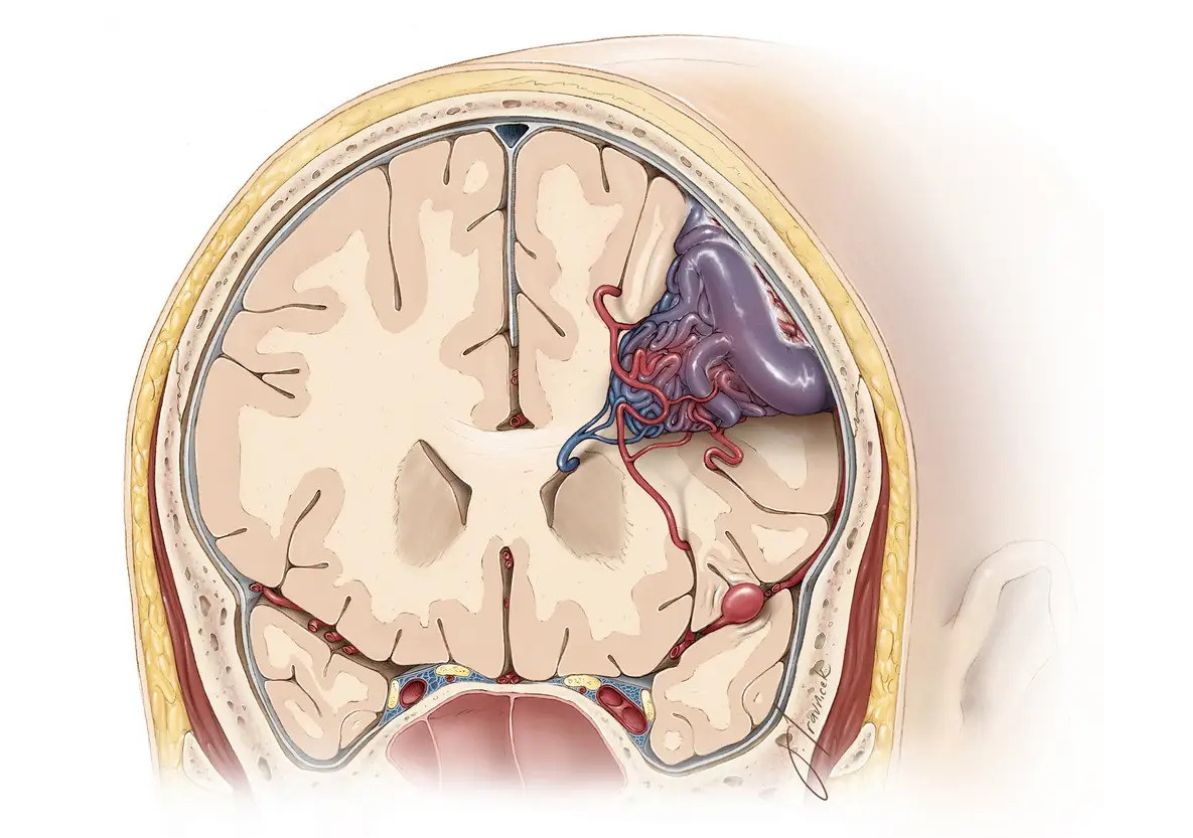

We specialize in the most challenging AVM cases, including:

•  Brainstem AVMs

•  Large or high-grade AVMs (Spetzler-Martin Grade III-V)

•  AVMs previously deemed "inoperable"

•  Spinal AVMs and fistulas

•  Cavernous malformations